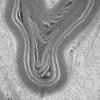

PERIPHERAL NEUROPATHY

12 ANTI-MAG NEUROPATHY (8)